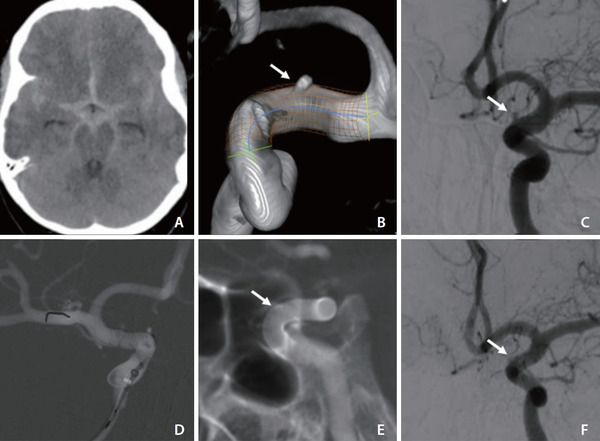

Early FD implantation in carefully selected ruptured aneurysms, including small saccular and morphologically complex lesions can achieve high functional recovery and complete angiographic occlusion, even in a resource-limited environment. Ideal case selection and standardized DAPT and hemodynamic protocols are critical. These findings support broader use in challenging aneurysms, but larger prospective studies are warranted to validate outcomes and refine management strategies.